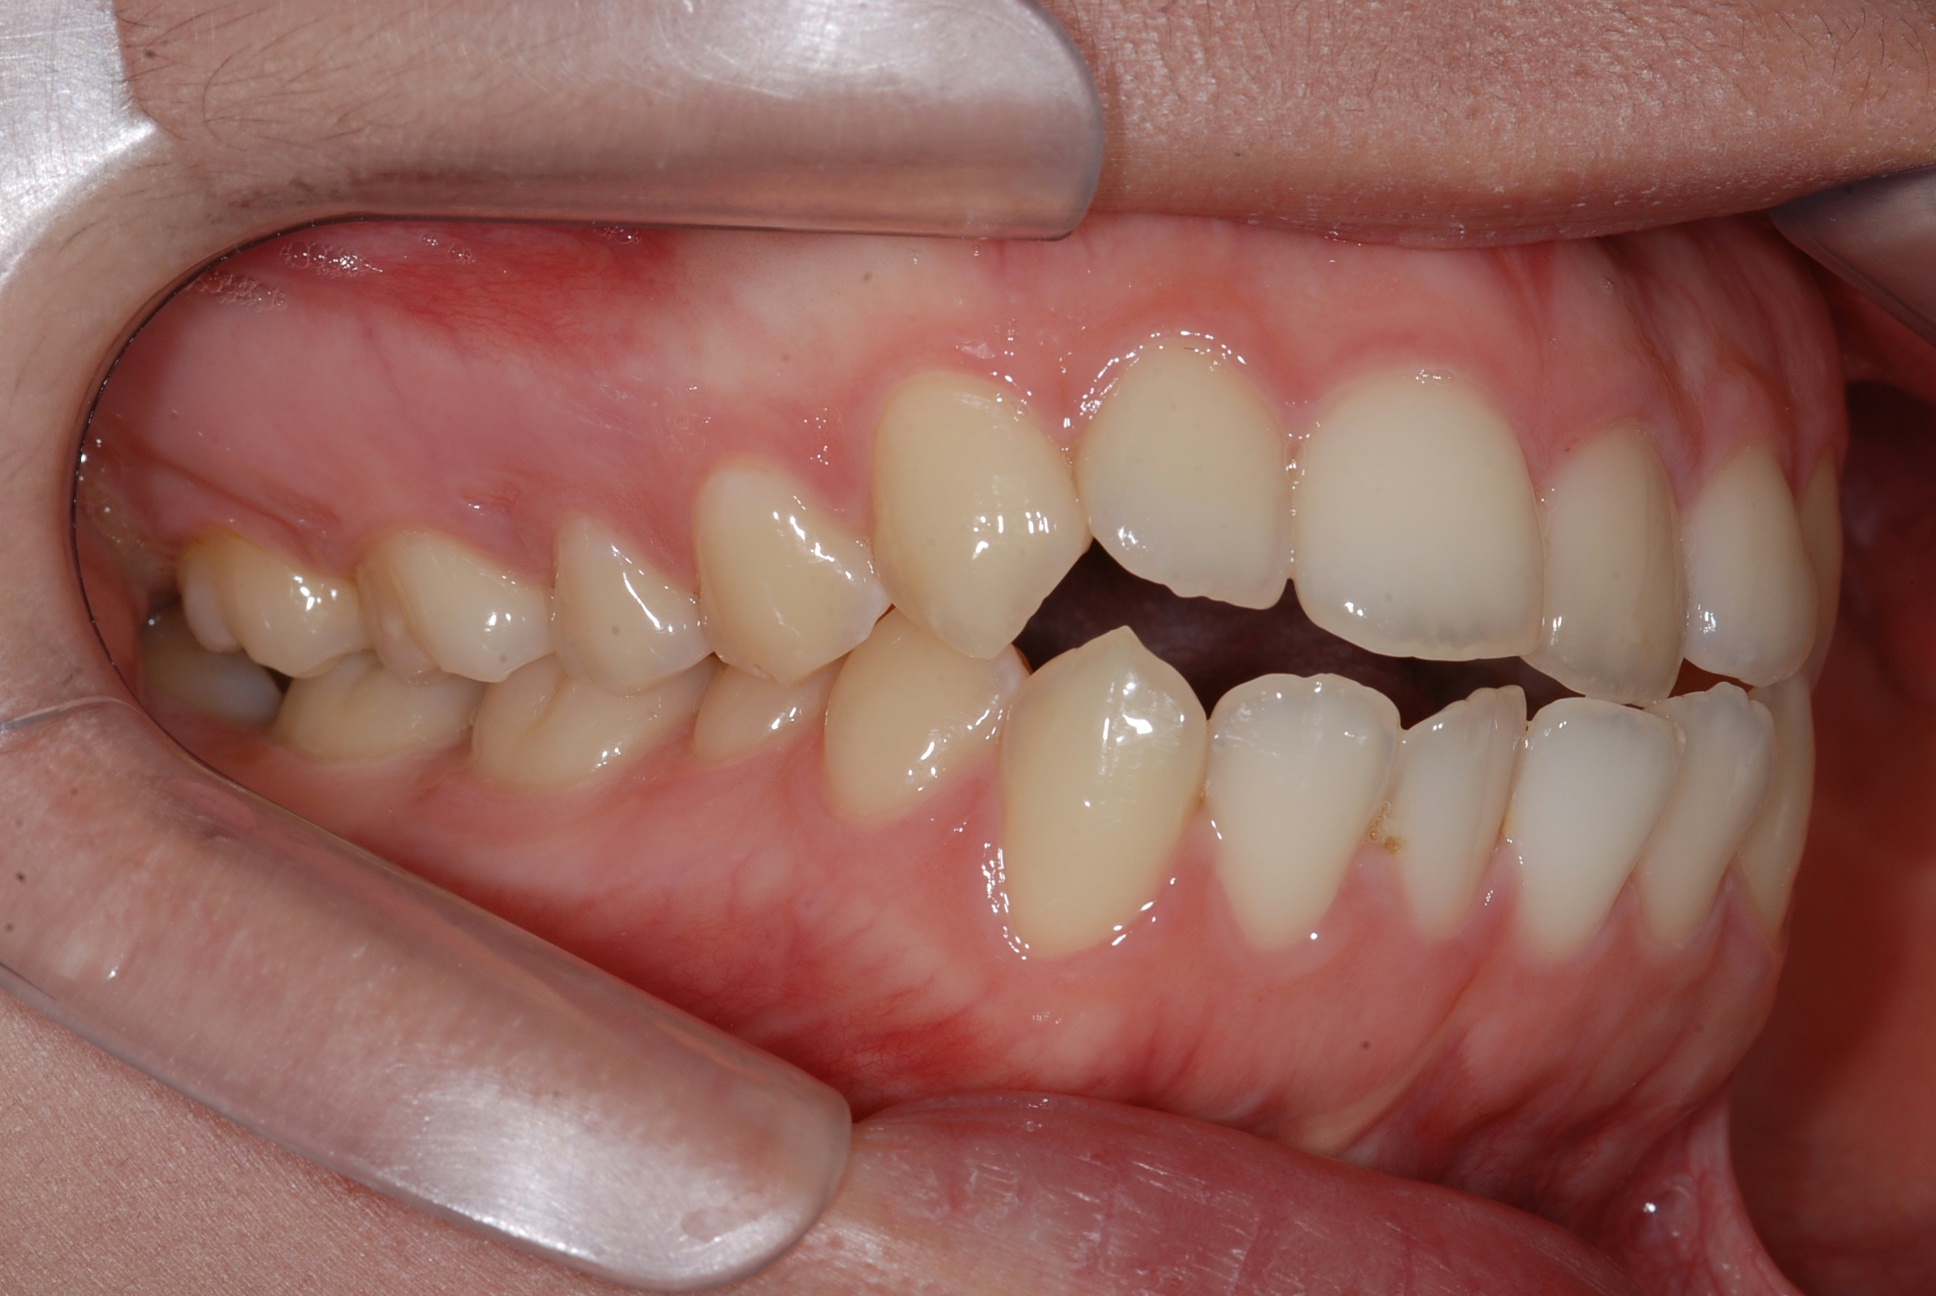

치료 전 사진입니다.